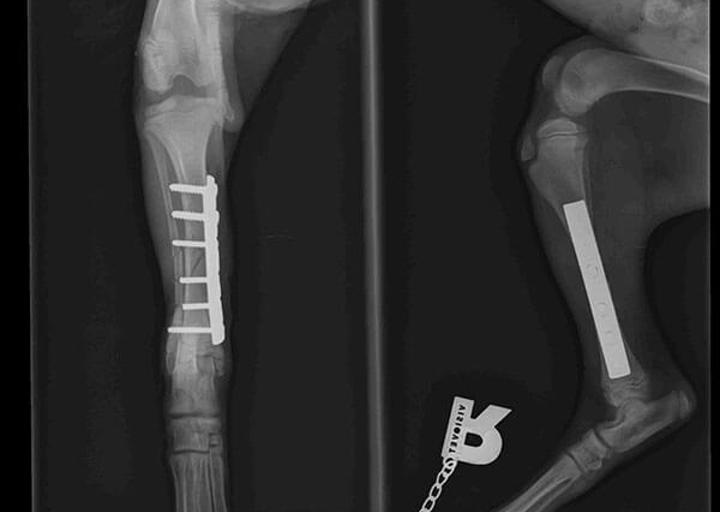

Baby Ray hatte Glück im Unglück, denn tierliebende Menschen haben ihn am Straßenrand liegend gefunden. Schnell war klar, dass Ray nicht laufen konnte, da sein Beinchen gebrochen war.

Natürlich wurde Ray so schnell wie möglich operiert. Die OP Kosten belaufen sich auf 240 €.